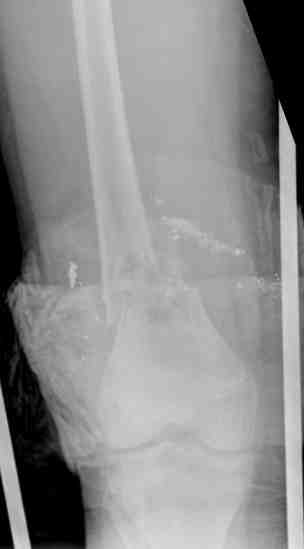

Послеоперационные рентгенограммы

Postoperative X-rays

В нижнем ряду представлены рентгенограммы после окончательной репозиции.

And final reduction after Hexapod program has been finished